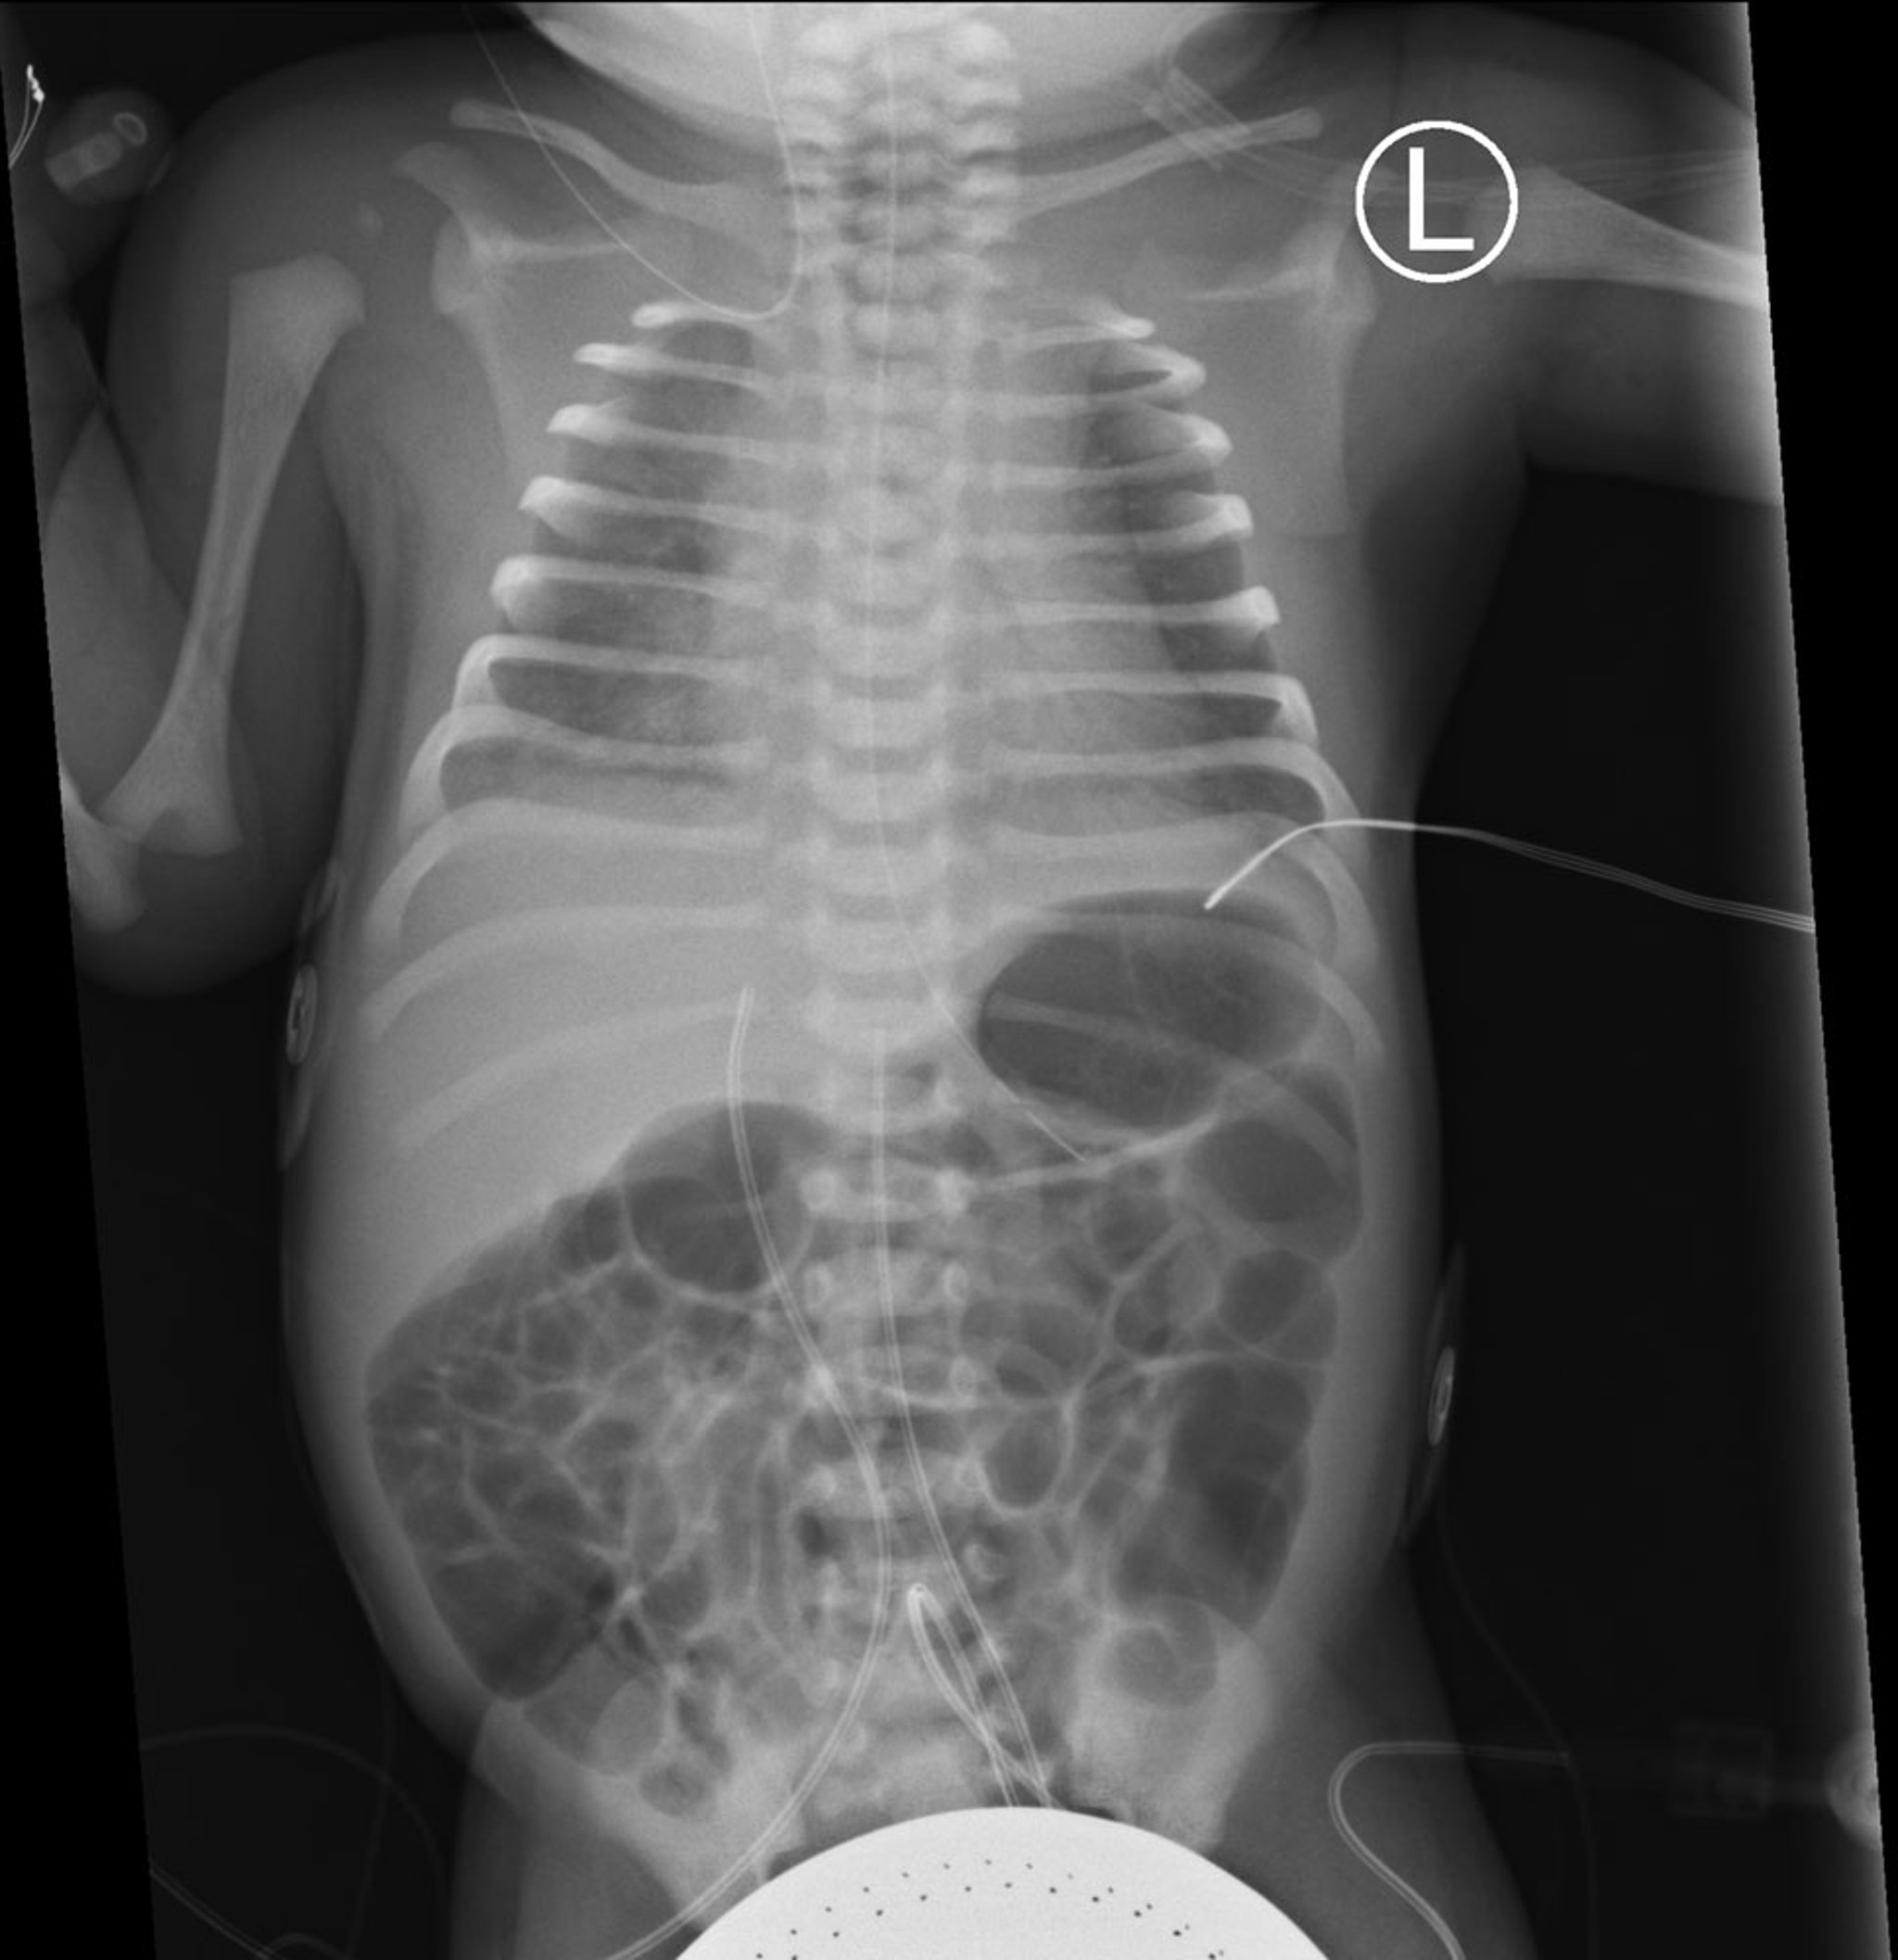

Diagnosis of RDS is by clinical presentation, including recognition of risk factors; arterial or capillary blood gases showing hypoxemia and hypercapnia; and chest radiograph. Chest radiograph shows diffuse atelectasis classically described as having a ground-glass appearance with visible air bronchograms and low lung expansion; appearance correlates loosely with clinical severity.

This frontal view of a chest and abdominal radiograph shows bilateral diffuse ground-glass opacity in both lungs with air bronchograms, consistent with respiratory distress syndrome (RDS).

Also seen are an orogastric tube as well as umbilical artery and venous catheters in expected positions.

Steven Needell/SCIENCE SOURCE/SCIENCE PHOTO LIBRARY